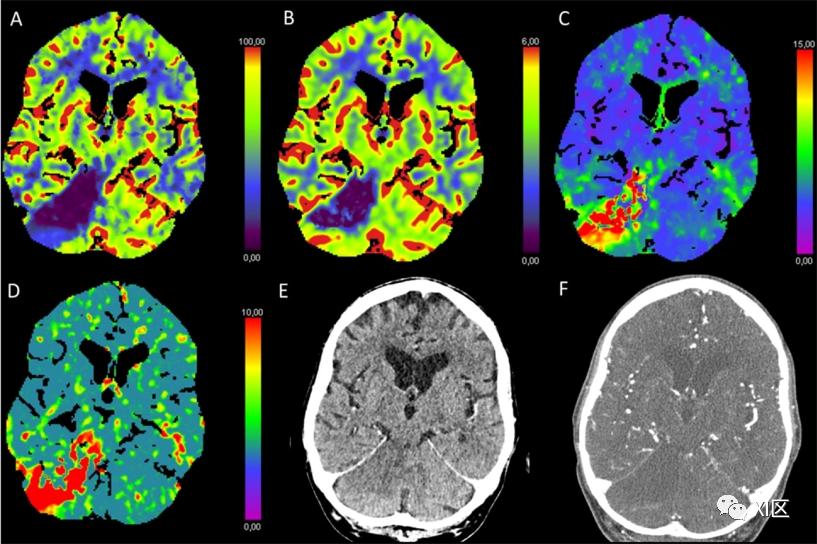

图7 脑部CTP产生的彩色编码图:(A)脑血流量(CBF)[mL/100 g/min],(B)脑血容量(CBV)[mL/100 g],(C)Tmax [s],以及(D)平均通过时间(MTT)[s]。(E)NECT和(F)动脉CT血管成像(CTA)。该患者在经导管主动脉瓣植入术(TAVI)后出现了视力模糊、运动失语和吞咽困难。在NECT图像上,右侧小脑上半球有轻微的低密度改变和肿胀,表明有急性梗塞。在CTP图上,CBF和CBV降低,Tmax和MTT延长。CTA显示右侧小脑上动脉缺失,在左侧部位是双倍的。这表明是完全闭塞,特别是考虑到该血管的增生非常罕见。3.3 全身缺氧缺血性损伤/脑死亡

心脏骤停是一个众所周知的全脑缺血的原因。在这方面,CTP已被应用于确认整体缺氧缺血性损伤或脑死亡后,在一些研究中证明了脑实质灌注的缺失。根据Monro-Kellie假说,颅内压升高会导致脑灌注减少,最后停止。毛细血管水平是脑循环停止的第一个地方,可以通过CTP观察到。可以观察到颅内动脉和静脉没有出现强化的情况。

在这种情况下,脑循环停止的最早迹象是大脑内深静脉和大脑大静脉没有强化。这一发现在CTA中诊断脑循环停滞的敏感性为98-100%。脑动脉环对比度缺失是脑循环停滞的一个不太敏感的指标,然而显示的敏感性为86-100%。

在文献中,CTA和CTP之间的相互矛盾的结果被描述为高达15%,CTA有时显示一些持续的颅内血流,而CTP显示脑灌注完全缺失。图8提供了一个例子。

图8 脑部CTP产生的彩色编码图:(A)脑血流量(CBF)[mL/100 g/min],(B)脑血容量(CBV)[mL/100 g],(C)Tmax [s],以及(D)平均通过时间(MTT)[s]。(E)NECT和(F)动脉CT血管成像(CTA)。除了颅骨骨折和蛛网膜下腔出血外,NECT显示大脑普遍肿胀,灰白质分化消失,脑脊液空间因普遍脑水肿而严重减少。根据CTP,没有检测到CBF或CBV。在CTA上,颅内动脉的造影剂仍然可见,但在静脉中几乎无法识别。CTP的时间衰减曲线显示,这并不是技术故障或方法问题的结果:动脉曲线有规律的增加(红线),但静脉曲线有一个平台(蓝线),很可能是由于缺乏实质的脑灌注(右半球:亮绿线;左半球:深绿线)。建议结合CTP和CTA,可以减少假阴性结果的数量(特别是单独使用CTA时)。造影剂停滞可能影响CBF和CBV图的ROI测量,所有的定量分析都应仔细评估。